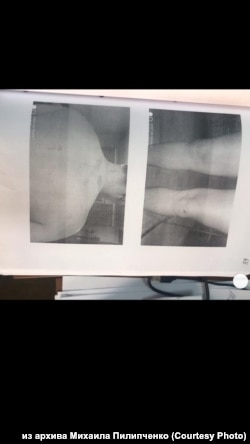

Побои Михаила Пилипченко, зафиксированные судмедэкспертом

– Конечно, я, получается, главный свидетель. Не исключаю, что именно из-за этого на меня уголовное дело завели – репутацию как свидетелю испортить. 17 июня меня вызвали как свидетеля. А буквально через несколько дней уже как подозреваемого опрашивали. Плюс следователь мне "забыла" выдать направление на судмедэкспертизу, а без нее ты побои не снимешь так, чтобы суд это принял. В итоге я только через месяц их снял, когда гематомы уже спали, синяки уже проходили.